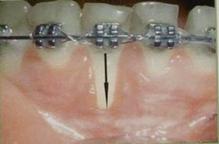

Отдельно следует выделить операции на пародонте и ортодонтическое лечение. Первые являются причиной в силу образования рубцов, потери нормального зубодесневого прикреплнения и нарушения трофики тканей, а неконтролируемое перемещение зубов и приложение чрезмерных сил могут приводить к образованию дигисценции альвеолярной кости, вследствие чего возникают рецесси.Лабиальное передвижение зубов во время ортодонтического лечения может быть причиной истончения вестибулярной десны и альвеолярной кости.Ортодонтические брекеты, проволочные ортодонтические конструкции затрудняют удаление зубного налета,

способствуют гингивиту.Рецессия десны — это одно из наиболее часто встречающихся осложнений ортодонтического лечения, причем оно сильнее выражено при применении форсированных методик лечения (рис. 5).Учитывая это обстоятельство, перед лечением ортодонт должен оценить ширину прикрепленной десны и при необходимости направить пациента на консультацию к пародонтологу. При малой ширине прикрепленной десны с вестибулярной стороны передних зубов до ортодонтического лечения рекомендуется проводить ее увеличение. Нетрудно заметить, что ятрогенными все эти факторы называются условно, а по своей сути являются травматическими.